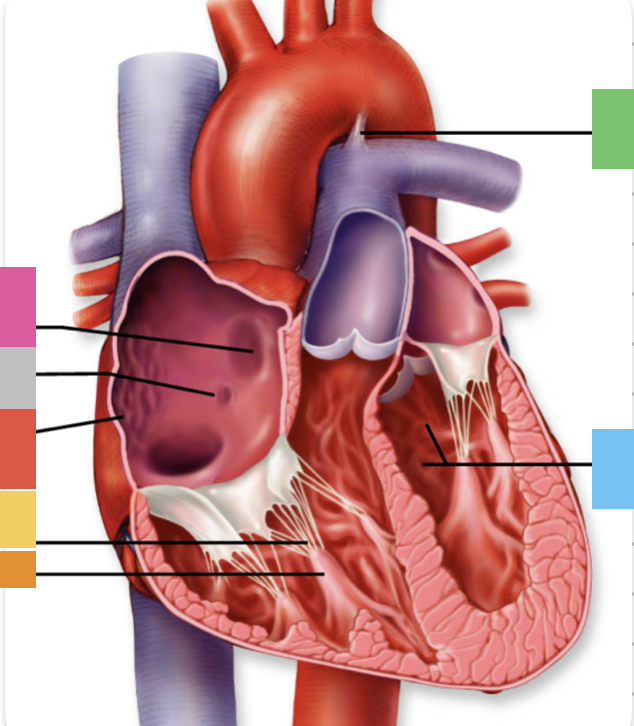

light purple

base

purple

apex

grey

right atrium

pink

right auricle

green

left atrium

green

left auricle

blue

right ventricle

orange

left ventricle

green

coronary (atrioventricular) sulcus

pink

interatrial septum

dark blue

interventricular septum

green

anterior interventricular sulcus

green

posterior interventricular sulcus

orange

aortic valve

yellow

pulmonary valve

red

tricuspid valve (right AV)

purple

bicuspid valve (left AV)

yellow

chordae tendineae

orange

papillary m.

blue

trabeculae carneae - only in ventricles

red

pectinate m. - only in R atrium

pink

fossa ovalis

grey

opening of coronary sinus